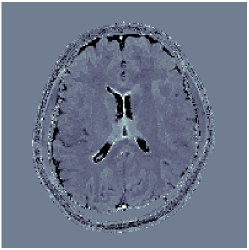

Two sets of experiments were conducted here: first, we used the 2D and 3D acquisition sequences for scanning a healthy volunteer’s brain (real-world acquisitions). Figures 6 and 7 display the parametric maps reconstructed from 2D spiral and radial readouts. We computed the T1, T2 and proton density (PD) maps using baseline reconstruction algorithms ZF, VS, LR, FLOR, AIR-MRF and our proposed LRTV. While baselines use DM either for quantitative inference or also during reconstruction (i.e. AIR-MRF), we further compare the DM-free LRTV’s performance when cascaded to DM, KM and MRFResnet for quantitative inference. For the 3D spiral acquisitions we compared LRTV and its closest competitor VS in Figure 8. Outcomes from other tested algorithm are displayed in the supplementary materials (Figure S5). Since FLOR does not use dimensionality-reduction, our system ran out of memory during 3D reconstruction; hence results are not reported in this case.

VI-E1 Discussion

The LRTV-DM and LRTV-MRFResnet perform on par, and both outperform all tested baselines for reconstructing T1, T2 and PD maps in all acquisition schemes. This can be observed both visually in Figures 6, 7, 8, S2 and S3, and quantitatively in Table IV across all tested metrics. Other baselines were unable to successfully remove the under-sampling artefacts in TSMIs, and these errors propagated to the parameter inference phase and resulted in inaccurate maps. Temporal-only priors incorporated within LR are shown insufficient to regularise the inverse problem and LR sometimes (e.g. 2D spiral acquisitions) can admit solutions with even stronger artefacts than the model-free ZF baseline. This issue was previously studied for other non-Cartesian MRF readouts that similar to our spiral/radial trajectories, miss to sample the corners of the k-space in all timeframes (see section 2.2.2 and figure 2 in [19]). In the absence of reference for the k-space corners information, the LR iterations despite minimising the objective can converge to solutions with high-frequency artefacts, as visible in the computed maps. This highlights the need for adding an appropriate spatial-domain regularisation. FLOR reduces the LR’s artefacts but this improvement is limited because the suggested nuclear norm penalty does not incorporate an explicit spatial regularisation. Further for reducing artefacts, FLOR can introduce an undesirable bias in the computed T1/T2 maps e.g. see error maps in Figures S2 and S3. The non model-based VS baseline incorporates spatial regularisation and results in spatially smoother maps than ZF and LR, but it is unable to output artefact-free images. Further and consistent with our in-vitro experiment, we observe that VS overestimates the T2 values (e.g. in White and Grey matter regions) in tested 2D acquisitions i.e. the spatial regularisation trades off agains the quantification accuracy. The model-based AIR-MRF adds spatial regularisation through 2D/3D low-pass Gaussian filters however this trades off the sharpness of the computed maps and can increase the errors at the tissue boundaries (we searched Gaussian spreads that keep the blurs and high-frequency artefacts minimal). For our acquisition readouts, Gaussian filters performed better than disk filters of [19] for avoiding strong Gibbs artefacts. On the other hand, the spatiotemporally regularised LRTV greatly improves the TSMI reconstructions i.e. 4 dB enhancement compared to the closest competitor baseline (Table IV). This enables computing accurate and aliased-free multi-parametric inference using DM or the DM-free learning-based alternative MRFResnet as visible in Figures 6, 7, 8, S2 and S3. MRResnet and DM score competitive quantitative inference results i.e. T1 and T2 MAPE less than 5% and 9%, respectively (Table IV). KM also outputs comparably accurate T1 maps, however this shallow learning model despite having a model size larger than MRFResnet, is unable to learn accurate T2/PD quantification and it results in poor estimated maps, consistent with our observations in section VI-C.